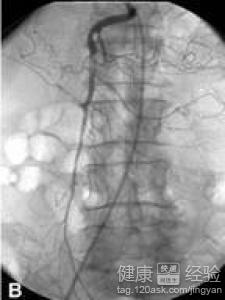

急性腸系膜血管缺血性疾病該如何治療?出現急性腸系膜血管缺血性疾病時,應該及早的去,診斷及早的治療,可以采用手術的方法來治療,急性腸系膜血管缺血性疾病,如果出現了腸壞死,那麼就應該做腸切除術,治療腸系膜血管缺血性疾病時,一定要注意這種疾病常會被誤診為腸梗塞,所以,在做臨床上的診斷是,要根據症狀的表現具體來分析。

3如果到了急性腸系膜血管缺血性疾病的嚴重期,就應該采用手術的治療方法,通過手術的治療方法,可以直接切除,我們壞死的腸管,避免患者產生大量的腹水造成患者,心率加快,呼吸急促的症狀出現。